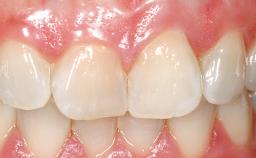

Late Flapless Placement of an Implant in a Maxillary Left Central Incisor Site

A 39-year-old male patient presented with a chief complaint of discomfort and gingival discoloration around his maxillary left central incisor. He was in good general health and was a non-smoker. His past dental history was significant because of the traumatic fracture of tooth 21 in a sporting accident at age 13. Initial dental treatment included endodontic therapy and a full-coverage restoration. The patient became symptomatic 5 years later, when structural failure of the tooth resulted in the dislodgment of the crown. Endodontic retreatment, apical surgery, and post-and-core restoration were performed.

Prosthesis Type FDP

Soft Tissue Contour and Volume Slightly compromised